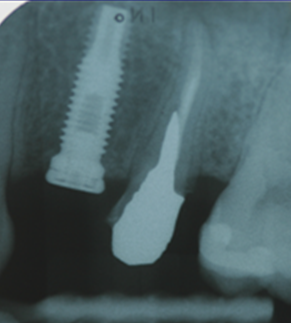

Ακτινογραφική εικόνα του εμφυτεύματος